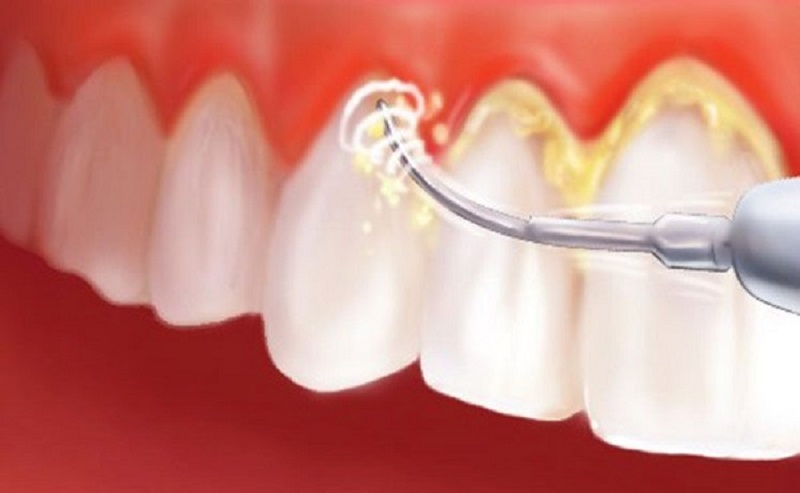

- Viêm nha chu mức độ nhẹ: Bác sĩ sẽ tiến hành loại bỏ mảng bám vi khuẩn, cạo vôi răng và làm sạch cao răng nhằm kiểm soát viêm nhiễm và ngăn bệnh tiến triển nặng hơn.